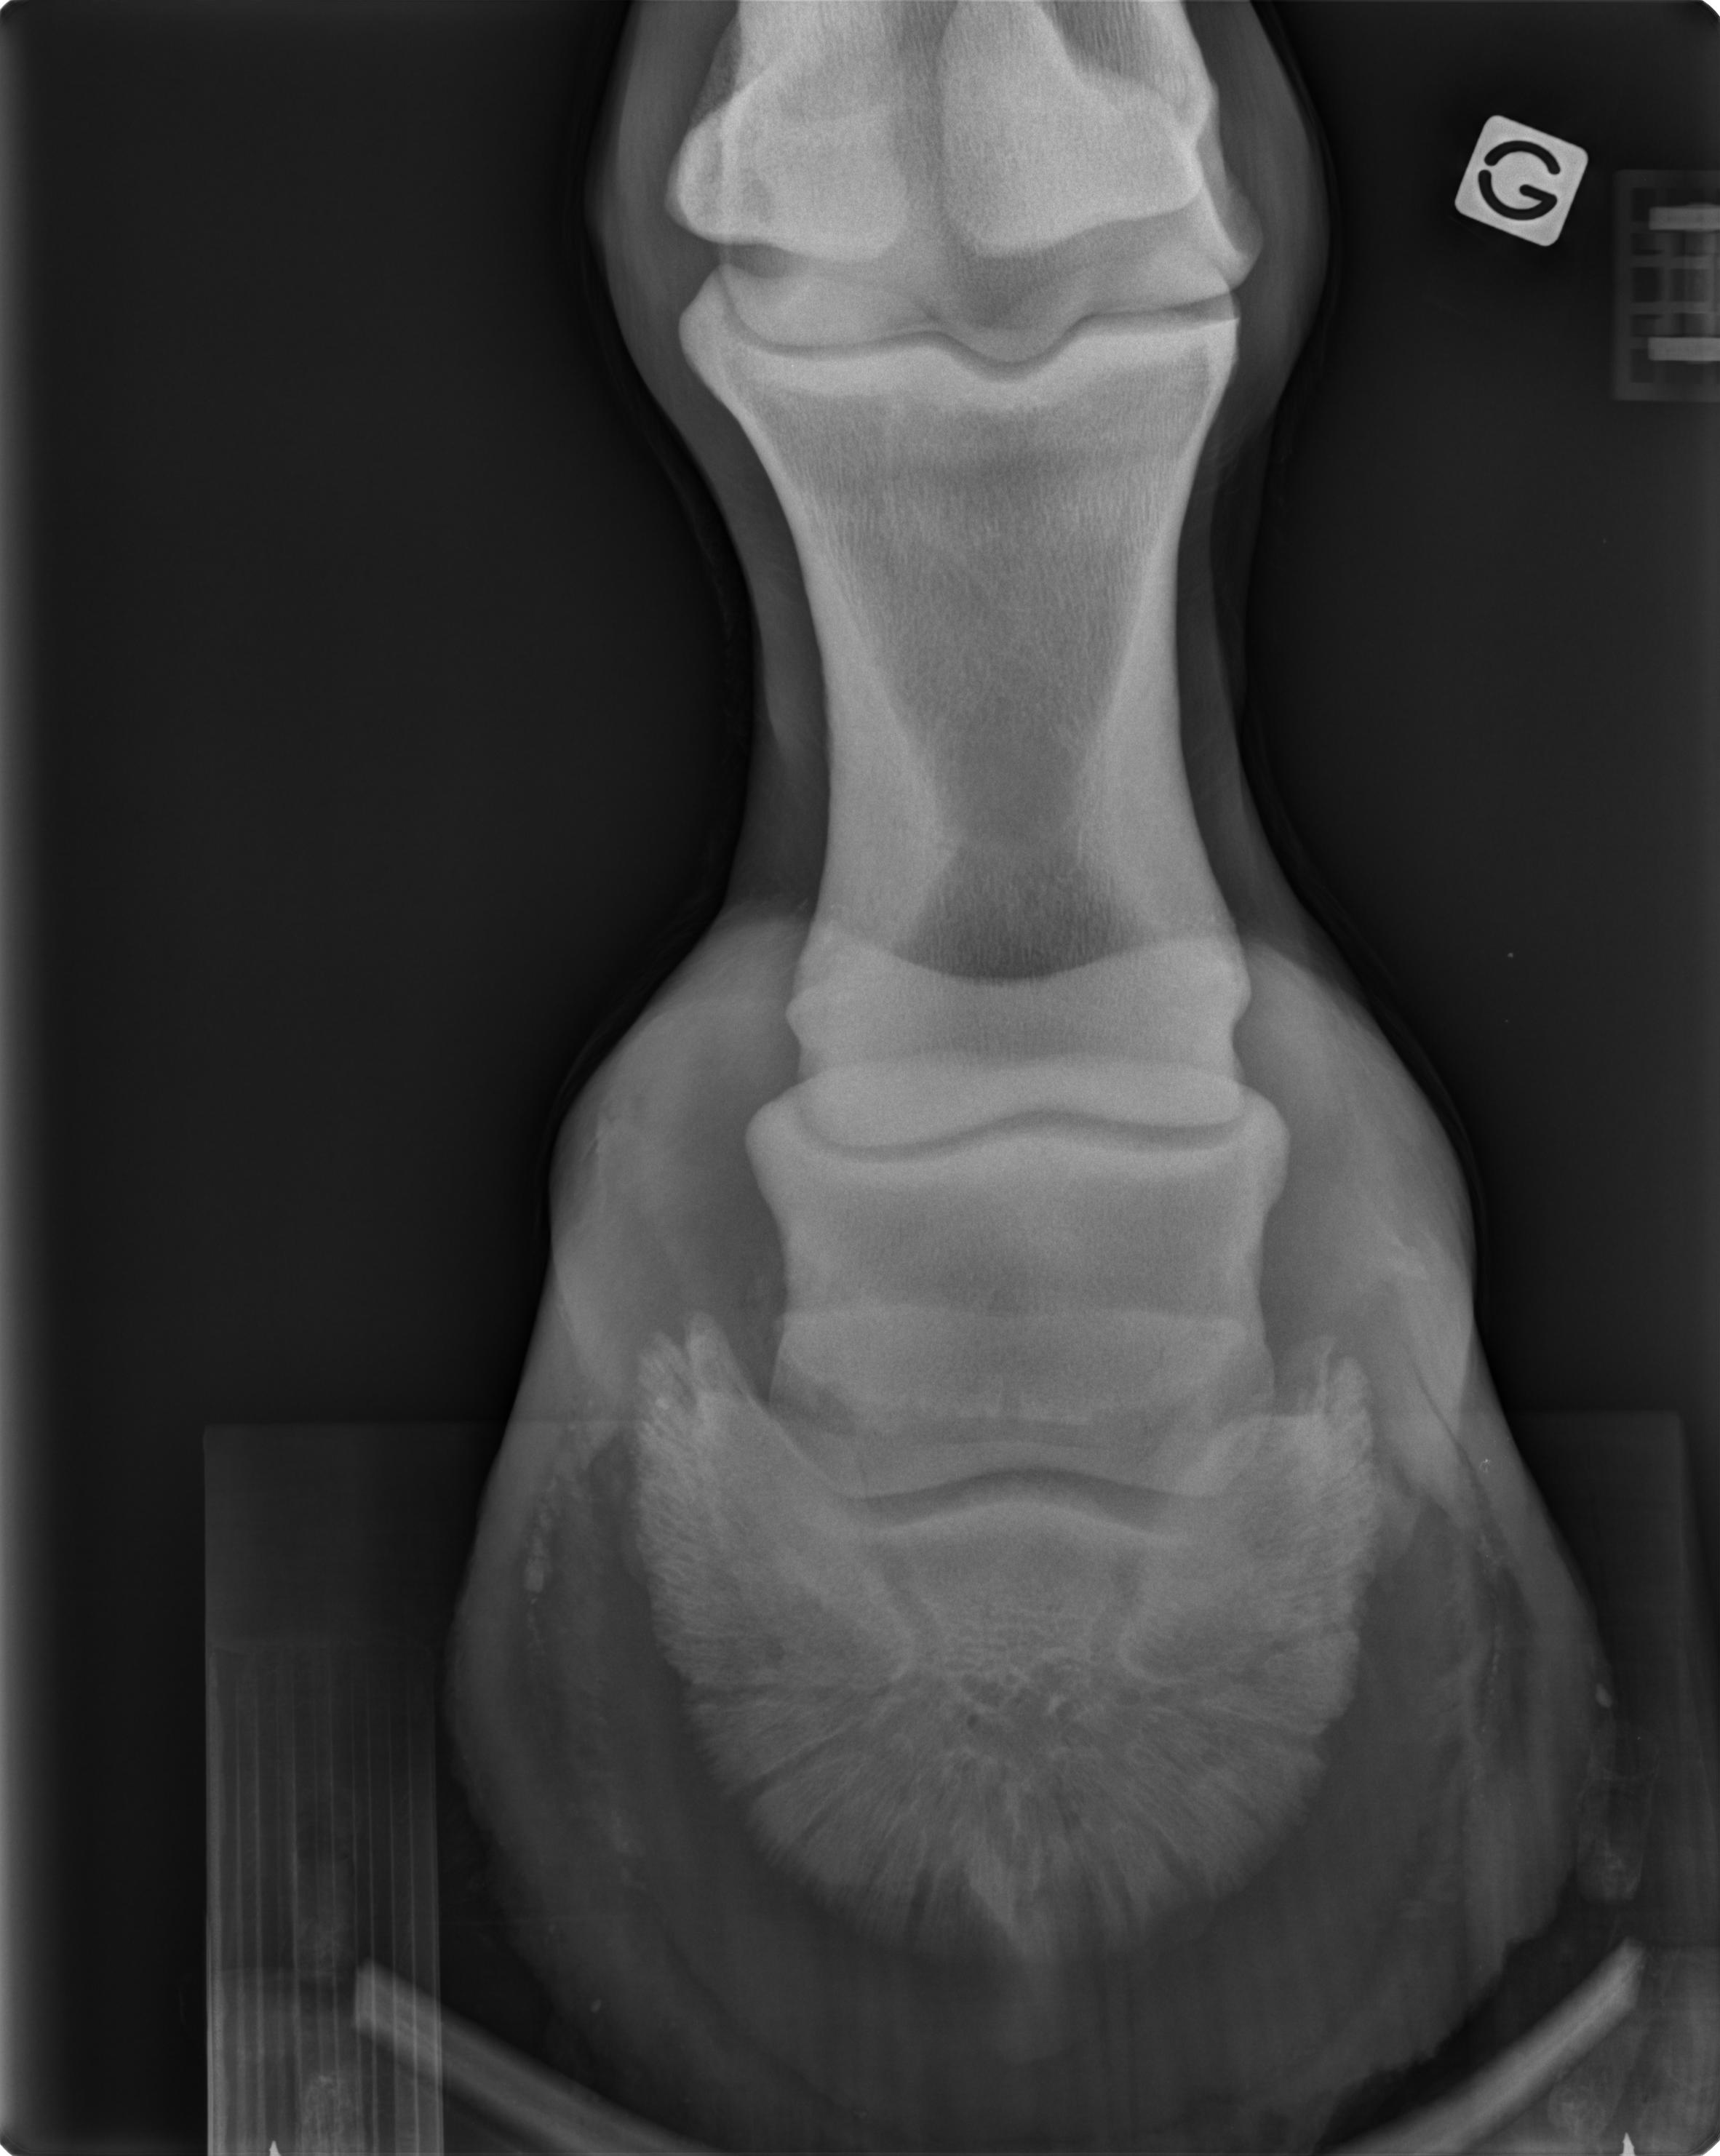

La clinique dispose d'un appareil de radiographie avec développement numérique permettant l'obtention rapide d'images de qualité. Les clichés sont réalisés à la clinique dans une salle assurant le comfort et la sécurité des chevaux et des intervenants.

Les radiographies peuvent être nécessaires notamment pour explorer une boiterie ou dans le cas de dépistage de pathologie ostéo-articulaires lors de vente ou d'achat d'un cheval.